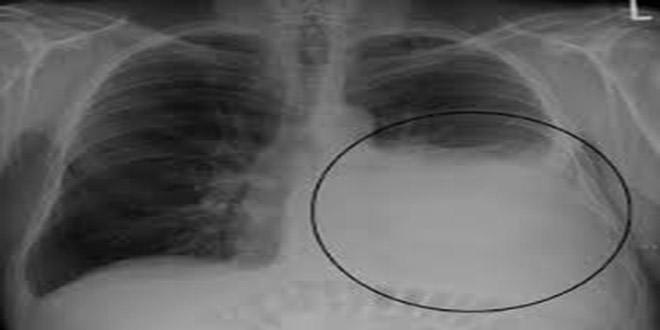

Tràn dịch màng phổi là sự tích tụ dịch bất thường trong khoảng giữa nhu mô phổi và thành ngực. Khoảng không này được gọi là khoang màng phổi. Khoảng một nửa số bệnh nhân ung thư sẽ bị tràn dịch màng phổi.

- X-quang ngực: giúp khảo sát hình ảnh dịch tích tụ bên trong cơ thể